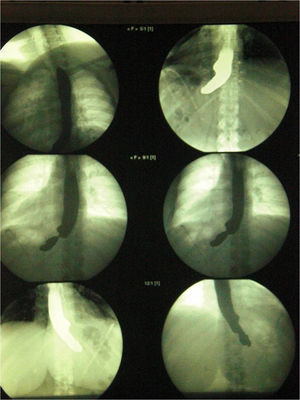

Paciente de 36 años con antecedentes personales de DM de tipo 2 y con un índice de masa corporal de 38kg/m2. Se interviene en nuestro servicio y se le realiza una GVL: tras la liberación de la curvatura mayor se introduce sonda de Faucher del número 36. Se comienza la sección gástrica a 5cm del píloro y se utiliza en las 2 primeras secciones cargas de 4,8mm y en el resto cargas de 3,5mm. Antes de la sección se comprueba que la sonda no está atrapada con la endograpadora. Posteriormente, se realiza una sutura invaginante de la línea de sección con monofilamento reabsorbible 2–0. Se comprueba estanqueidad con azul de metileno y se deja colocada una sonda nasogástrica durante 24h. El postoperatorio inmediato es favorable, a excepción de que la paciente no traga la saliva. En el tercer día postoperatorio se realiza un tránsito (como protocolo general de nuestra unidad de cirugía bariátrica). En este se observa una estenosis completa en el tercio proximal de la tubulización (fig. 1). Pensando en que pudiera ser consecuencia del edema posquirúrgico, se propone nutrición parenteral y se decide esperar una semana para realizar una segunda prueba mediante radiología intervencionista. En ella se evidencia claramente el stop completo en tercio proximal, que se confirma por gastroscopia al evidenciar un fondo de saco a unos 3cm de la unión gastroesofágica que impide el paso del endoscopio.

El postoperatorio de la paciente es favorable y se la da de alta a los 7 días de la segunda intervención. En los controles posteriores (tránsito un mes posterior al alta) se observa un paso y adecuado de contraste a través de la anastomosis (fig. 2).